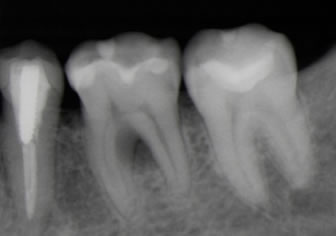

トンネリングと同様、歯の根の枝分かれした部分に歯石が付着した際の治療法です。

「ルートセパレーション」は、歯を2〜3個に分割して、歯石を清掃しやすい状態にする治療法です。最終的には分割した歯にかぶせ物をして、見た目や機能性も回復させます。

ヘミセクションは、ルートセパレーション後に残った2根のどちらかを抜歯し、最終的には歯にブリッジをして、見た目や機能性も回復させます。

トライセクションは、ルートセパレーション後に残った3根の1〜2根を抜歯し、最終的には歯にかぶせ物をして、見た目や機能性も回復させます。

ルートアンプテーションは、トライセクションの際に、歯冠を残し、歯根のみを抜歯し、最終的には歯にかぶせ物をして、見た目や機能性も回復させます。